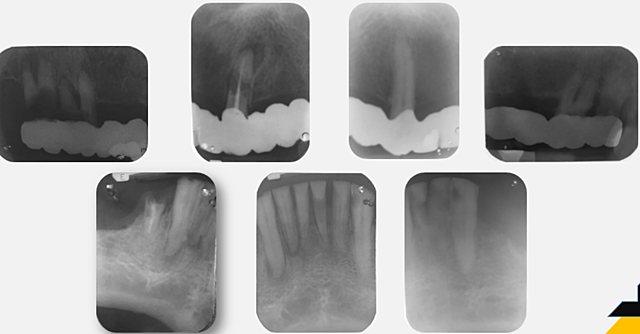

• RADIOGRAFÍA PERIAPICAL

RADIOGRAFÍA PERIAPICAL

Se observo zona radiolucida en tercio medio del OD 3.1, lesión apical en OD 4.3, fractura en tercio medio del OD 1.3, ensanchamiento del ligamento periodontal en OD 2.3 y exposición de furca en OD. 1.8 y 1.7.